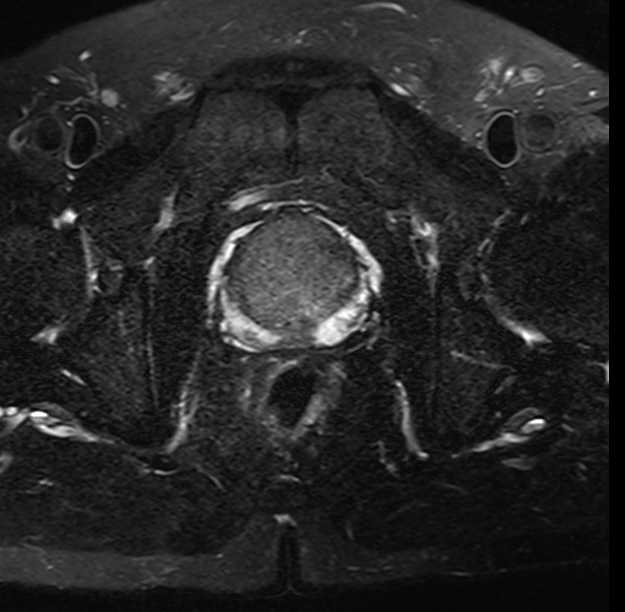

70歲的患者林大伯,揭西人,因反複的尿頻、尿急及排尿困難要求手術治療收住院。經前列腺特異抗原篩查、前列腺MRI增強掃描,考慮前列腺癌。後經前列腺穿刺活檢術,确診爲高分化前列腺癌。

△前列腺MRI增強掃描